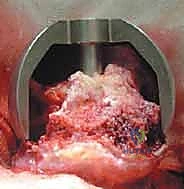

3. نحت وتشكيل رأس عظمة الفخذ

بدلاً من قطع الرأس، يستخدم الجراح أدوات ميكروسكوبية ومثاقب دقيقة جداً لإزالة الغضروف التالف وطبقة رقيقة من العظم المريض، ليتم "نحت" رأس العظمة ليصبح جاهزاً لاستقبال الغطاء المعدني بشكل مثالي.

5. تحضير وتلبيس تجويف الحُق (Acetabular Component)

يتم تنظيف تجويف الحوض (الحُق) من الغضاريف المتآكلة باستخدام مبشرة طبية، ثم يزرع وعاء معدني (Cup) داخل التجويف. هذا الوعاء يثبت عادة عن طريق الضغط (Press-fit) حيث ينمو العظم الطبيعي لاحقاً حوله ليثبته بقوة.